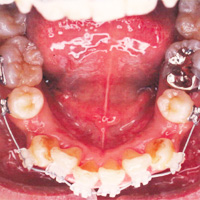

- 幼児期の矯正・・・乳歯のみ萌出している2,3 歳の頃に治療を行います。主に受け口を治します。

- 学童期の矯正・・・乳歯と永久歯が混ざって萌出している8,9 歳位の頃にスタートします。

実際お口の中に装置が入ります。

患者様の状態により、上だけ付ける場合と上下付ける場合があります。